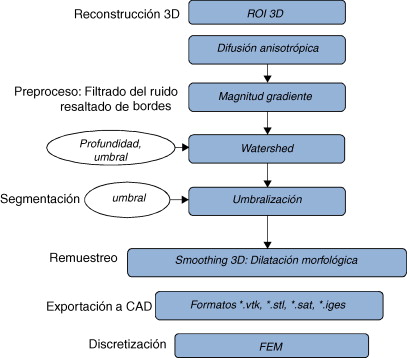

2. Conceptualización y metodología

El problema de obtener modelos geométricos a partir de imágenes médicas implica la utilización de un conjunto de rutinas de procesamiento aplicadas a la matriz 3D de las imágenes médicas a lo largo de varias etapas de procesamiento. En la figura 1 se observan las cinco etapas propuestas con las herramientas de software utilizadas en cada una de ellas, las cuales son: (1) etapa de lectura y reconstrucción, en la cual se implementó una rutina para obtener una imagen 3D de dimensiones m × n × o obtenida por el apilamiento paralelo de o cortes ortogonales (axial, coronal o sagital) del mismo tamaño de m × n pixels , donde cada elemento de la matriz representa un valor de intensidad de gris calculado por la interacción de la radiación en el tejido. (2) Preproceso, en la cual se aplicaron rutinas de suavizado de ruido y realzado de bordes, de este modo se mejoró la calidad de las imágenes, preparándolas para la siguiente etapa. (3) Segmentación, en la cual se utilizaron rutinas de extracción del volumen de los tejidos u órganos de interés. (4) Remuestreo, donde se emplearon rutinas de posprocesamiento para suavizar las superficies y eliminar elementos no conectados presentes en los volúmenes segmentados. (5) Exportación de modelos, para lo cual se implementaron rutinas para almacenar los volúmenes obtenidos en formatos legibles por herramientas de visualización médica y CAD, en las cuales se visualice en sólidos, superficies, mallas, etc.

Figura 1. Esquema de procesos y rutinas implementados en una herramienta de procesamiento de imágenes médicas desarrollada en MATLAB [13] . |

Para la obtención de los modelos geométricos y la interacción con los algoritmos de procesamiento considerados en este trabajo, se desarrolló una herramienta computacional [13] bajo la plataforma de MATLAB [12] , en la cual se integraron las rutinas por etapas (fig. 1 ).

A continuación se describen los algoritmos de procesamiento considerados por cada una de estas etapas, y como fueron implementados en este trabajo.

Las rutinas presentadas en el apartado anterior fueron aplicadas en imágenes médicas, orientados por flujogramas de algoritmos establecidos para las etapas representadas en la figura 1 . A continuación presentamos los resultados obtenidos en cuatro casos de estudio.